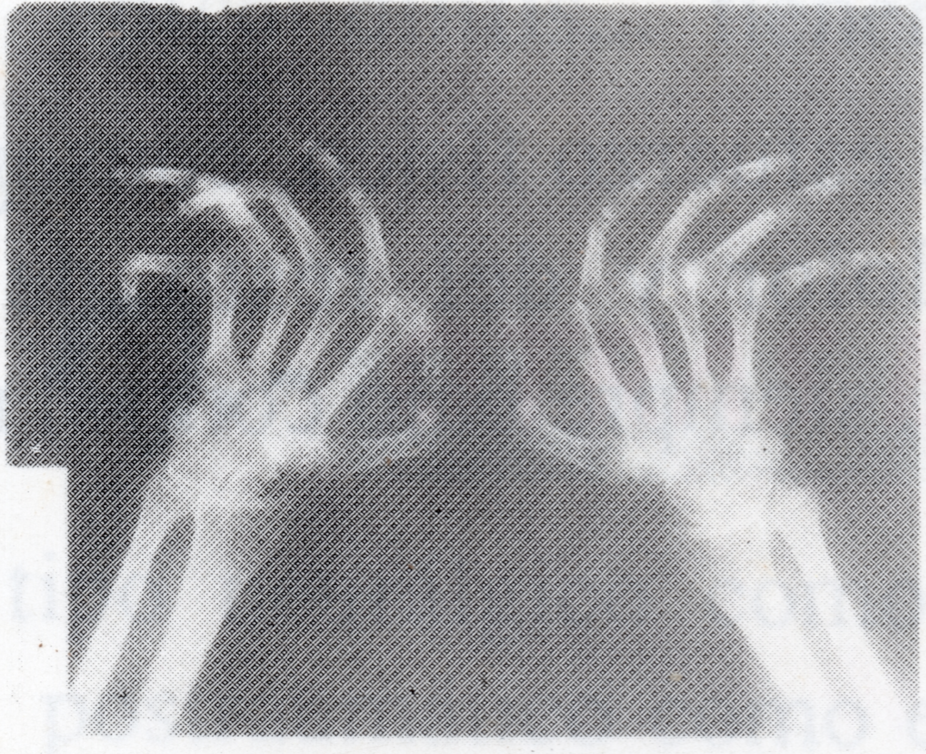

TRATAMIENTO DE LA ARTRITIS REUMATOIDE MEDIANTE RCE

Bozidar Konjevic, descubridor de la RCE, padeció esta enfermedad durante 25 años hasta su invalidez total certificada. Por este motivo desarrolló esta técnica con la que recuperaría la movilidad total y su salud. La RCE ha logrado la remisión de esta enfermedad que se considera incurable. Las radiografías muestran la gran mejoría de un paciente tras cuatro meses de tratamiento.

ANTES

DESPUÉS